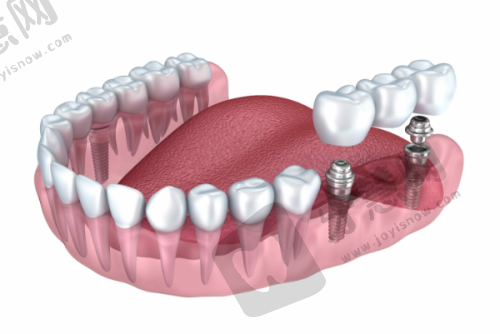

你是否正在为寻找一家靠谱的北京种植牙医院而烦恼?北京中诺口腔医院在当地声名远扬,凭借特色的技术实力、丰富的临床经验和优质的服务态度,赢得了广大患者的信赖和好评。特别是在种植牙领域,更是众多患者的优选之地。接下来,让我们深入了解北京中诺口腔医院种植牙的相关信息。

北京中诺口腔医院种植牙成功实例分享

众多成功实例见证实力:北京中诺口腔医院有特别多种植牙成功实例。老大爷牙齿全掉光,刘忠祥医生为其制定全口种植方案,术后能正常吃饭,身体修复健康。年轻女士前牙缺失,潘火青医生为其进行前牙美学区种植修复,牙齿美观,女士变得自信。